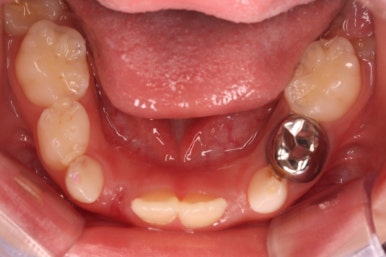

부산어린이치아교정 키다리아저씨치과에 처음 내원하셨을 당시의 입안의 모습입니다. 네 군데 모두 어금니는 보이지 않습니다.

입 안에서 문제점이 발견되지 않는 경우 일이 커지는 경우가 많은데 이번 환자분은 X-ray를 찍어봄으로써 문제를 조기에 발견하고 치료를 할 수 있었습니다.

X-ray 촬영이 신의 한수 였던 것이지요.